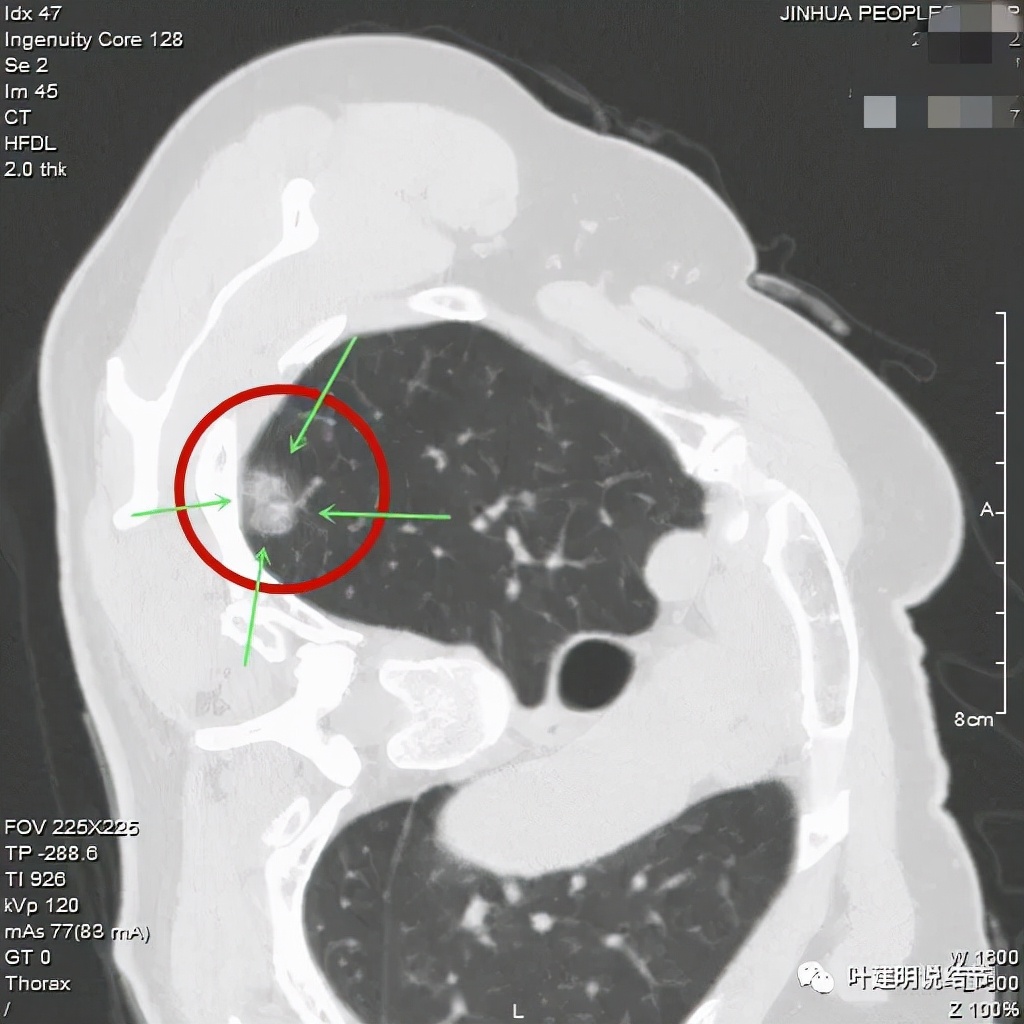

可见左肺上叶磨玻璃结节,边缘略显模糊,瘤肺边界不是很清,但总体上看,病灶轮廓仍是较为清楚的,而且有所层面有微小血管进入,病灶密度也不均匀,感觉有点杂乱。这种病灶如果随访了2个多月仍持续存在,也没多少变化的话,基本上要考虑肿瘤范畴的结节。为了看细节,我们建议其再查了靶扫描,图像如下:

病灶密度较低,膨胀性略,瘤肺边界在靶扫描上还是显得有些清晰的